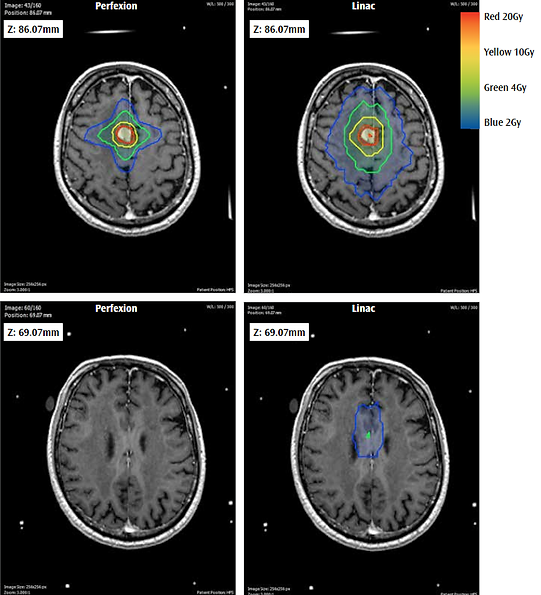

Гамма нож метастаз